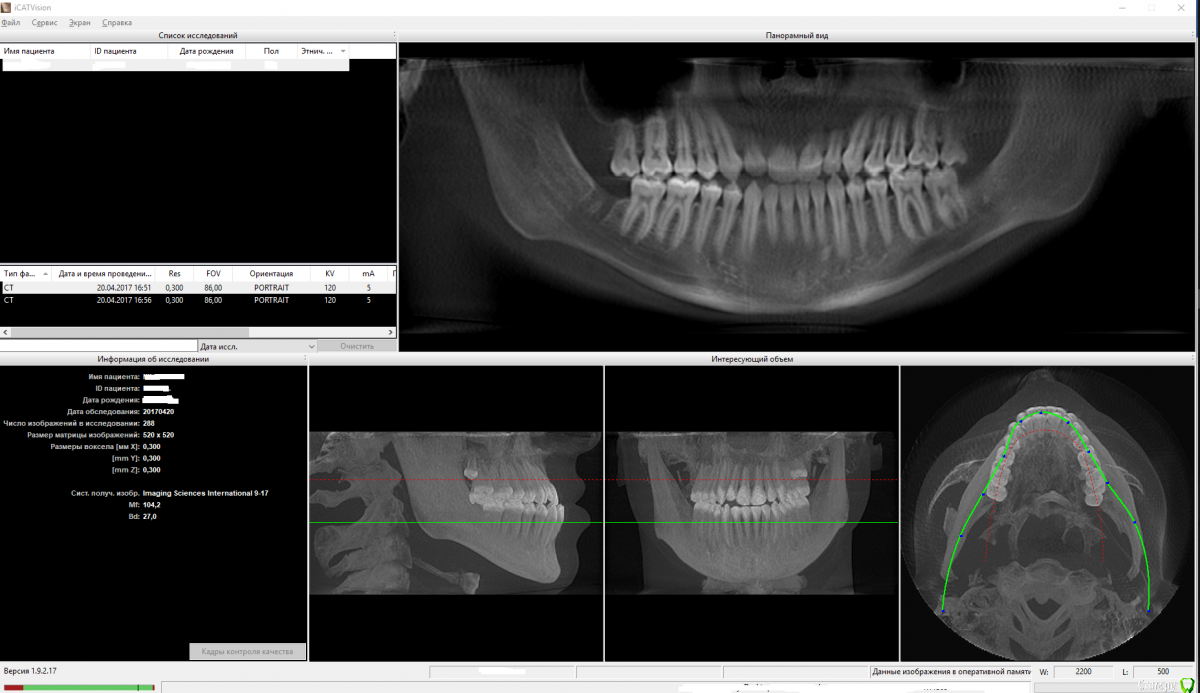

Ness Опубликовано 23 апреля, 2017 Поделиться Опубликовано 23 апреля, 2017 Добрый вечер! Сыну в феврале исполнилось 17 лет. В конце весны прошлого года стали интенсивно расти нижние восьмерки. Каюсь, недоглядел. Каким-то непостижимым образом за год нижняя челюсть сильно выдвинулась настолько, что ему стало тяжело есть и значительно ухудшилась дикция.Пошли к ордотонту, который немедленно порекомендовал удалить эти восьмерки, что и было сделано. Далее, консультировались у трех разных ортодонтов и двух челюстно-лицевых хирургов.Первый ортодонт (который собственно и сказалал удалять восьмерки) порекомендовал удалить нижние четверки и попытаться брекетами сдвинуть зубы несколько назад. Но, как мы с сыном поняли, проблему это не устранит, т.к. нижняя челюсть то останется выдвинутой.Двое остальных ортодонтов сказали - без вариантов только хирургия.Настала очередь консультироваться у хирургов. Сделали КТ.Здесь мнение хирургов разделилось. Один рекомендует ТОЛЬКО укоротить нижнюю челюсть и задвинуть её. Второй говорит, что верхняя челюсть недоразвита и двигать нужно ОБЕ ибо если подвинуть ТОЛЬКО нижнюю, то через несколько лет она опять выдвинется вперед.Мы с сыном в полном затруднении. Перелопатили массу информации, но разобраться тяжело. Прошу помощи советом у профессионалов - как наиболее целесообразно поступить в данной ситуации?Из программы (которую нам дали вместе с диском) ICatvision я сделал два снимка экрана нижней и верхней челюсти (файлы .dcm в наличии есть, но пока я их, согласно правилам, никуда не выгружаю без дополнительных требований со стороны врачей) и прикрепил к сообщению здесь.Также на следующей недели пообещали дать еще .dcm файлы (обработанные), которые нужно будет просматривать другой программой - SimPlant O&O Viewer.Но может можно на основании тех данных что уже есть подсказать нам какое решение в нашей ситуации будет более предпочтительным? Операции, конечно, боимся. Но сын морально готов, лишь бы это убрало проблему с прикусом, речью, жеванием, дыханием и пр.Заранее спасибо большое за уделенное время! Ссылка на комментарий